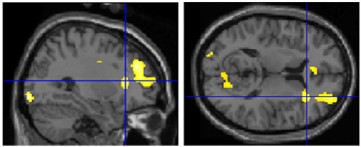

1) canonical sculptures activated right insula (mediates emotions; connects to/from amygdala): evidence for _________ beauty (“I can see why people like that.”)

right insula activity

2) beautiful images activated right amygdala (responds to learned emotional information): evidence for __________ beauty (“I like that.”)

right amygdala activity

- conclusion: both of these non-mutually exclusive processes contribute to appreciation of artwork